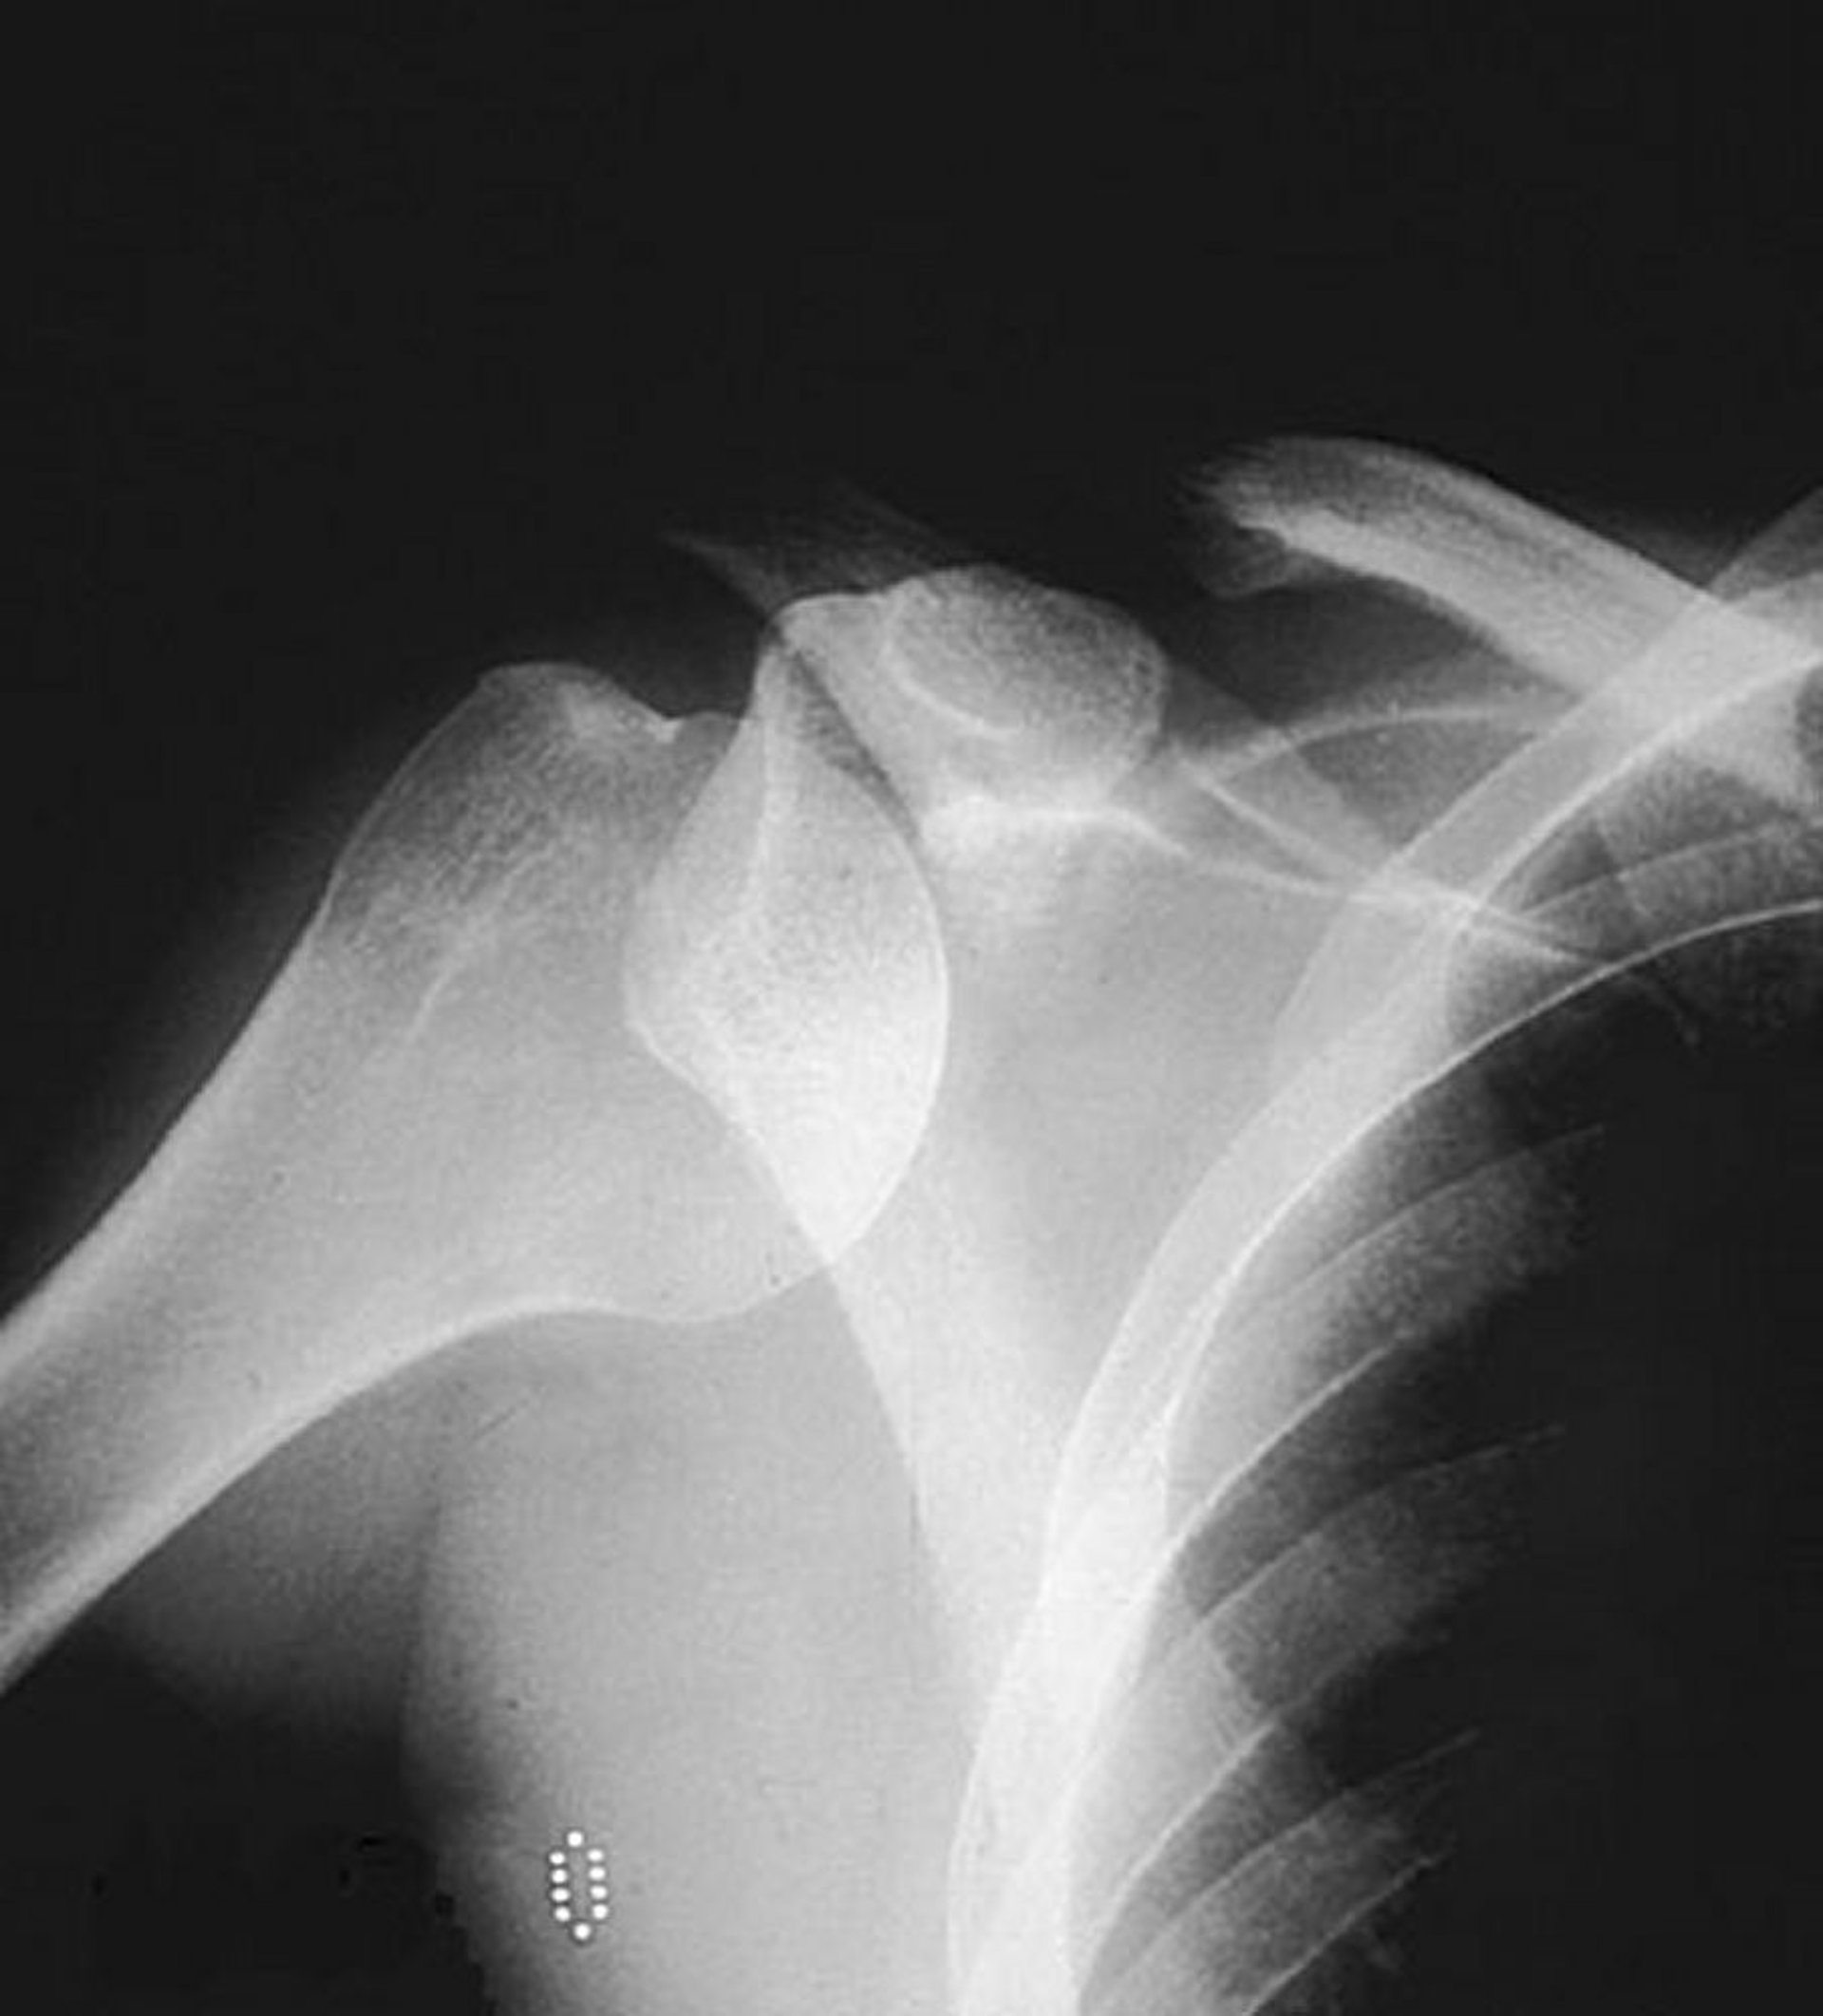

Luxação glenoumeral anterior (ombro)

Uma radiografia simples em incidência ântero-posterior mostra a cabeça do úmero fora de sua localização usual no interior da cavidade glenoidal, sugerindo uma luxação anterior.

By permission of the publisher. From Jacobs P: Current Orthopedic Diagnosis and Treatment. Editado por JD Heckman, RC Schenck e A Agarwal. Philadelphia, Current Medicine, 2002.